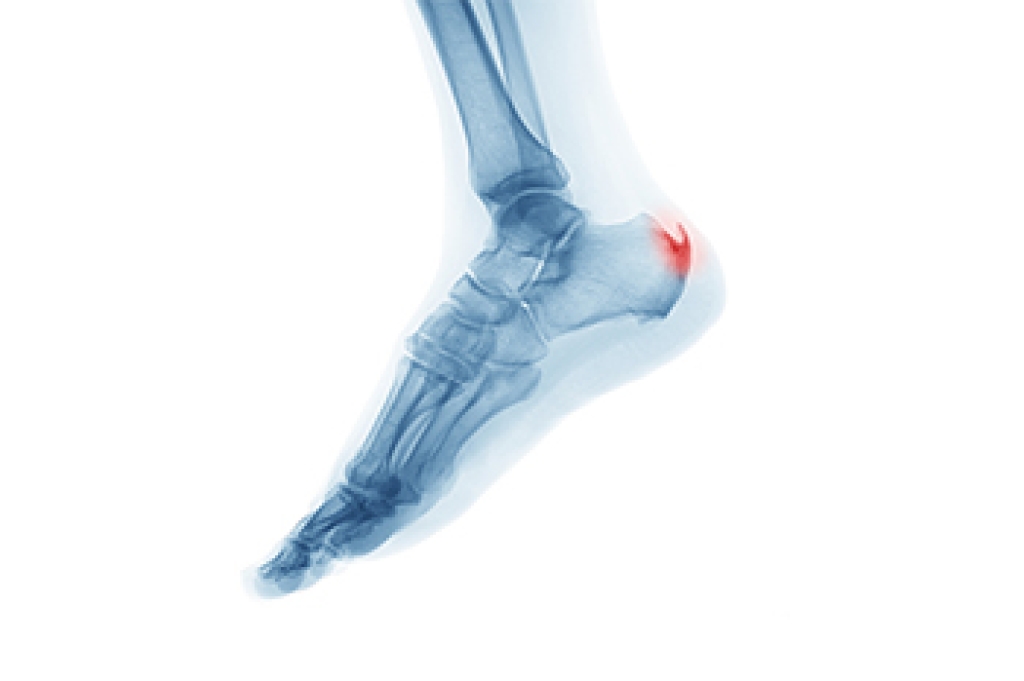

Heel Spur Pain

Heel spurs are bony growths that develop on the heel due to stress and inflammation in surrounding tissues. They are commonly seen in two forms. Heel spur syndrome affects the bottom of the heel, and insertional Achilles tendinitis affects the back of the heel where the tendon attaches. Risk factors include flat feet, high arches, excess weight, tight calf muscles, and repetitive impact activities. Symptoms may involve sharp heel pain, stiffness, and discomfort during the first steps of the day. A podiatrist can diagnose the condition, offer custom treatments, and provide guidance to relieve pain and improve function. If heel pain is limiting your daily life, it is suggested that you consult a podiatrist who can offer effective relief and treatment solutions.

Heel spurs are formed by calcium deposits on the back of the foot where the heel is. This can also be caused by small fragments of bone breaking off one section of the foot, attaching onto the back of the foot. Heel spurs can also be bone growth on the back of the foot and may grow in the direction of the arch of the foot.

Older individuals usually suffer from heel spurs and pain sometimes intensifies with age. One of the main condition's spurs are related to is plantar fasciitis.

Pain

The pain associated with spurs is often because of weight placed on the feet. When someone is walking, their entire weight is concentrated on the feet. Bone spurs then have the tendency to affect other bones and tissues around the foot. As the pain continues, the feet will become tender and sensitive over time.